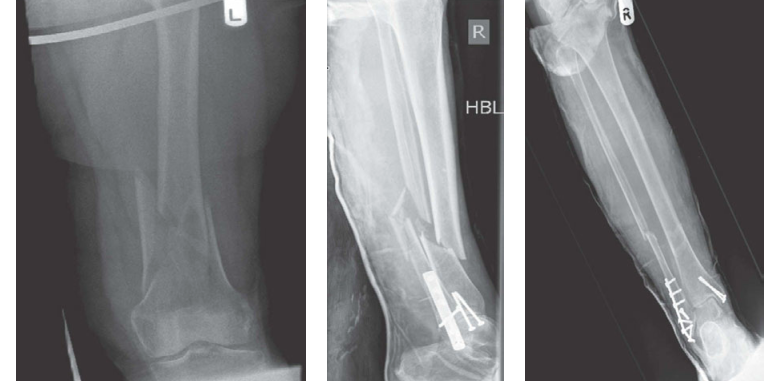

Lower limb Trauma Structured oral examination question 4 A 33-year-old roofer fell from a height of 20-feet, …